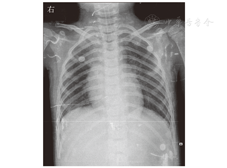

患儿男,6岁1个月,因"咳嗽、喘息3 d,加重伴嗜睡半天"于2019年9月29日入郑州大学附属儿童医院。患病以来,患儿精神差,食欲差,大小便未见明显异常。有反复咳嗽、喘息病史,入院前半个月患儿有肺炎病史,否认肝炎、结核等传染性疾病史及传染病接触史,已接种乙型肝炎疫苗、卡介苗、百白破混合疫苗、脊髓灰质炎灭活疫苗、麻疹减毒活疫苗等;患儿为第2胎第2产,足月顺产,姐体健,否认有家族性遗传病史。入院体格检查:体温为38.5 ℃,脉搏为175次/min,呼吸为42次/min,血压为99/63 mmHg(1 mmHg=0.133 kPa);呈浅昏迷,压眶皱眉,全身皮肤、黏膜无苍白、发花等,弹性正常;浅表淋巴结未触及肿大;双侧瞳孔等大,直径约3 mm,对光反射灵敏;在鼻导管吸氧下口周明显发绀,口腔黏膜光滑,咽充血,扁桃体Ⅱ度肿大,未见脓苔;颈软无抵抗,呼吸促,鼻翼煽动、三凹征阳性,双肺可闻及大量喘鸣音及中细湿啰音;心音有力、律齐,未闻及杂音;腹部软,稍膨隆,未扪及包块,肝脾肋下未及。四肢末梢暖,下肢无水肿,毛细血管再充盈时间为2 s,手足、肛周未见疱疹。膝腱反射和腹壁反射均未引出,四肢肌张力低,肌力3级,双侧巴宾斯基征、布鲁津斯基征、克尼格征均阴性。入院后初步诊断:重症肺炎,呼吸衰竭;中毒性脑病?病毒性脑炎?血常规检查:白细胞计数为10.28×109/L,血小板计数为356×109/L,中性粒细胞比例为0.81,淋巴细胞比例为0.12,CRP为1.50 mg/L,ESR为35 mm/1 h,降钙素原为0.09 μg/L。动脉血气分析:二氧化碳分压为36.6 mmHg,氧分压为56.6 mmHg。血生物化学检查:乳酸脱氢酶为119 U/L,肌酸激酶为10.06 μg/L,CK-MB为1 823 μg/L,肌钙蛋白为0.094 μg/L,B型钠尿肽前体为1 029 ng/L,血尿素氮为4.9 mmol/L,血肌酐为10.6 μmol/L。肝功能检查:总胆红素为13 μmol/L,DBil为7 μmol/L,ALT为22.3 U/L,AST为29.6 U/L,总蛋白为59 g/L,白蛋白为38 g/L。钾为3.7 mmol/L,钠为134 mmol/L,离子钙为1.20 mmol/L,氯为99 mmol/L,血糖为6.9 mmol/L,乳酸为1.2 mmol/L。血培养阴性,细菌毒素动态定量检测<5 ng/L,血清EB病毒早期抗原IgG和EB病毒衣壳抗原IgM均阳性,EB病毒衣壳抗原IgG和核抗原IgG均阴性,EB病毒DNA为3.28×105拷贝/mL。脑脊液压力为1.4 kPa,脑脊液常规检查:无色、清晰、透明,潘氏试验阴性,白细胞计数为0.095×109/L。脑脊液生物化学检查:氯为125.0 mmol/L,葡萄糖为3.0 mmol/L,蛋白质为277.9 mg/L,脑脊液腺苷脱氨酶为0.6 U/L。脑脊液EB病毒核酸DNA为5.61×106拷贝/mL。血液中S100蛋白为7.05 μg/L,神经元特异性烯醇化酶为75.25 μg/L。床边胸部X线片(图1)提示肺炎。床边脑电图检查:背景节律广泛漫波化异常,频发弥漫性慢波。入院第2天头颅MRI检查(图2)显示:双侧额颞顶枕叶皮质有线状弥散加权成像(diffusion weighted imaging,DWI)高信号,提示细胞毒性水肿。入院后立即给予心电监护,经皮氧饱和度检查,有创血压持续监测,气管插管、呼吸机辅助通气,美罗培南抗感染,甘露醇、甘油果糖、呋塞米等降颅压,静脉注射人免疫球蛋白、阿昔洛韦抗病毒治疗。患儿病情无好转,意识障碍加重,浅昏迷逐渐进展为深昏迷。入院后第7天复查头颅MRI(图3),双侧大脑半球、小脑、脑干弥漫性肿胀,呈广泛DWI高信号,脑沟变浅、鞍上池、环池、桥前池闭塞,脑干受压,小脑扁桃体下缘变尖,向下疝入上段椎管内,脑室系统明显变窄,提示弥漫性脑水肿、小脑扁桃体疝,颞叶沟回疝。入院第14天复查头颅MRI(图4)显示:弥漫性脑水肿,肿胀较前略减轻;小脑扁桃体疝,颞叶沟回疝;小脑半球内侧面脑沟略深,并皮质液体衰减反转恢复(fluid attenuated inversion recovery,FLAIR)稍高信号,考虑趋于脱髓鞘改变可能性大;双侧大脑半球硬膜下出血,蛛网膜下腔出血。患儿病情危重,治疗效果差,深昏迷无好转迹象,20 d后死亡。死亡诊断:EB病毒性脑炎、脑疝,重症肺炎,呼吸衰竭。